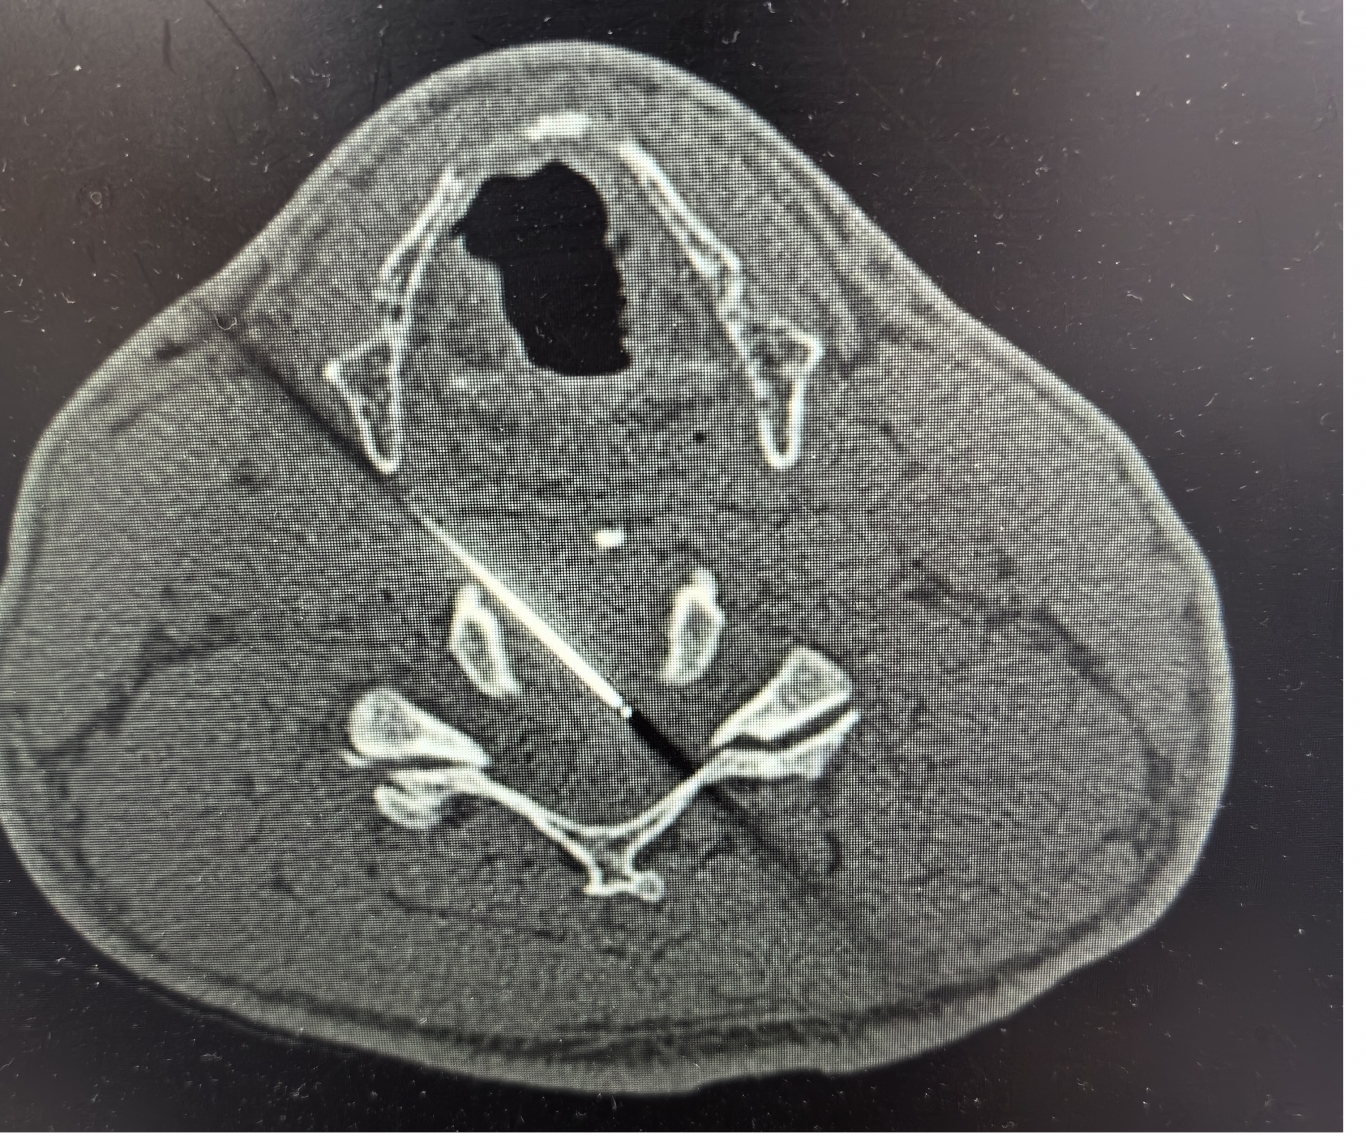

手術(shù)之后3天,黃大伯疼痛得到很好緩解,露出了許久沒有的笑容,終于可以安心躺著睡覺了,1個月后基本恢復了正常生活,6個月后復查CT發(fā)現(xiàn)突出的頸椎間盤已經(jīng)基本消失了,黃大伯一家人對治療效果非常滿意。

手術(shù)之前CT,巨大突出物 術(shù)后6個月復查CT:突出物消失